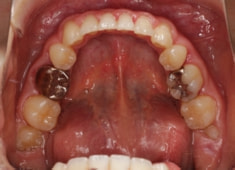

先天欠如歯両側上顎3番

治療法:フルパッシブブラケット:T21

治療前